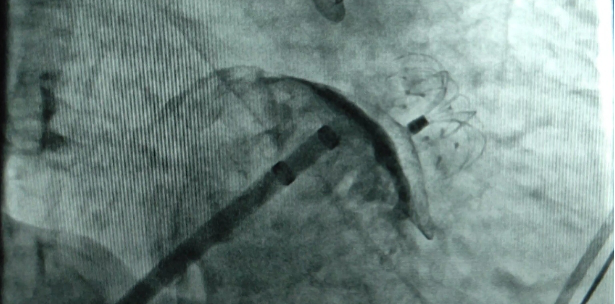

2021年8月9日14:30,手术正式开始。陈建华教授、王伟伟教授带领蓝文聪主任进行房间隔穿刺,并对患者左右肺静脉进行了射频消融,手术成功,患者恢复窦性心律。随后,由方军教授带领蓝文聪主任对患者进行左心耳造影,造影提示为风向标型左心耳。在精确测量左心耳开口宽度和深度后,选择了2632封堵器,经输送鞘管送至左心耳成功封堵。DSA透视下多体位造影显示无明显分流,床边心脏超声观察封堵器位置正确,心脏各组织结构均无受影响。两个手术共历时2小时多,手术顺利完成。随访一个月,患者无不适,恢复良好。